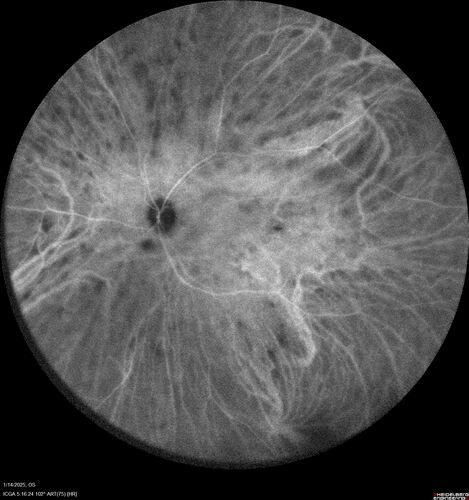

Birdshot Chorioretinitis - Chronic Untreated with Drusen Like Material in Macula

72 year old female with vision changes for years just now diagnosed with Birdshot.